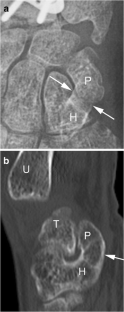

Fig. 2